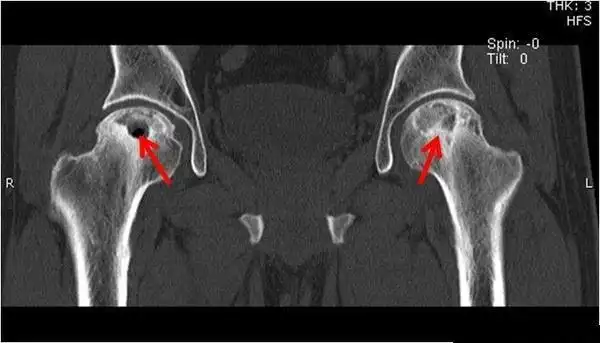

关节间隙狭窄,髋臼出现坏死变化,囊性变,囊肿和骨刺Ⅳ期c 新月征长度>